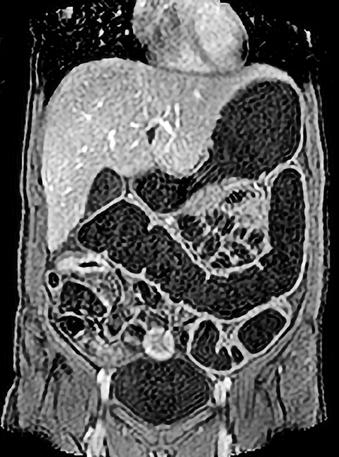

Rolul CT-ului în managementul cancerului rectal

Tomografia computerizată (CT) este una dintre primele investigații imagistice recomandate după confirmarea diagnosticului de cancer rectal. Aceasta poate oferi și unele informații despre invazia tumorală locală, dar rolul ei principal astăzi constă în evaluarea extensiei la distanță a bolii, fiind excelentă pentru identificarea metastazelor pulmonare și hepatice. CTul permite o evaluare rapidă și detaliată a cavității abdominale și toracice, având un rol cheie în stadializarea TNM (Tumor, Node, Metastasis) a cancerului.

Protocolul de examinare prin CT include utilizarea substanței de contrast intravenoase pe bază de Iod pentru a evidenția tumora primară și leziunile secundare. Examinarea durează, în general,

aproximativ 10-20 de minute, în funcție de complexitatea cazului și de necesitatea explorării mai multor regiuni anatomice. În mod uzual, în cadrul stadializării inițiale sunt evaluate toracele, abdomenul si pelvisul. De menționat că investigația CT este una iradiantă pentru pacient, raportul risc-beneficiu fiind totuși net în favoarea efectuării acesteia la pacienții diagnosticați cu cancer rectal.

Examinarea CT poate fi combinată cu tomografia cu emisie de pozitroni (PET), formând o tehnică de imagistică hibridă cunoscută sub numele de PET-CT. Aceasta presupune injectarea unui radiotrasor, de obicei fluorodeoxiglucoză (FDG), care se acumulează în zonele cu activitate metabolică crescută, tipică celulelor tumorale. Imagistica PET evidențiază aceste regiuni metabolice active, în timp ce CT-ul suprapus oferă detalii anatomice precise. PET-CT este o tehnică avansată, rezervată unor cazuri selectate, deosebit de utilă în stadializare în privința leziunilor secundare sau recidivei tumorale.

Metastaze pulmonare. Examen CT multislice, fereastră pulmonară, plan axial.

Din colecția Centrului de Imagistică, UMFCV